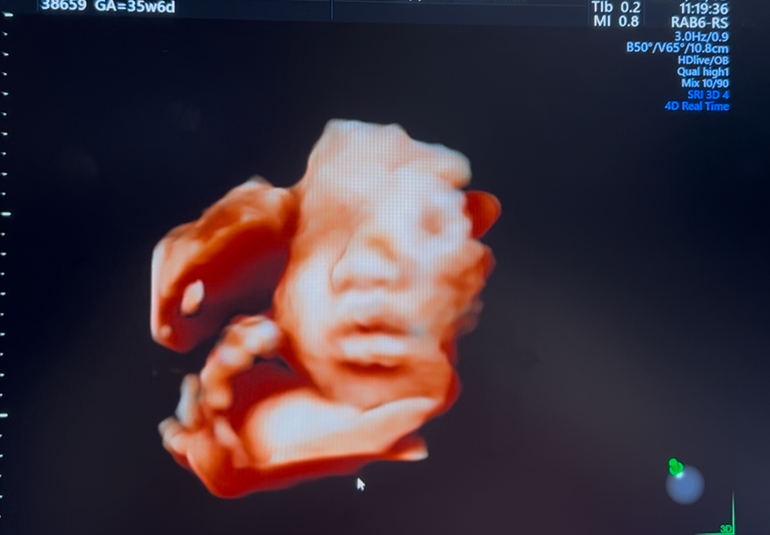

35週6日の妊婦です。

妊婦健診で4Dのエコー写真を撮って頂けるのですが、

顔の特徴がダウン症の特徴と同じのような感じがして

不安です。鼻は低いし目がつり目?のような浮腫んでるような…。

エコー写真を見るのが怖くて検診が億劫になってしまいます。

病院の先生にはなんのご指摘もされず、心臓の部屋?も4つあって元気とは言われておりますが、エコー写真の顔だけが心配です。

※写真は28週、35週、32週の順です。

実際にエコー写真でダウン症顔貌かの判断は、できないかなと思います。私からみて、エコーでみる赤ちゃんの顔としては、特徴的な顔貌の印象はないです。

エコー画像は、実際に見る感じとは、少し違う感じに見えるかなと思います。